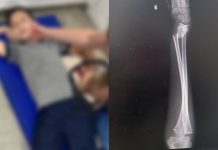

Mãe acusa negligência de escola em Joinville após filho de 9 anos quebrar o...

Acidente aconteceu na segunda-feira